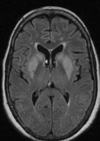

CADASIL As imagens do FLAIR mostram achados clássicos em CADASIL - hiperintensidades da substância branca confluentes com infartos lacunares e envolvimento dos lobos temporais anteriores

Do que se trata a CADASIL

Arteriopatia cerebral autossômica dominante com infartos subcorticais e leucoencefalopatia (CADASIL). Acomete adultos jovens (40 - 60 anos) e cursa com infartos subcorticais da substância branca, recorrentes com demência subcortical lentamente progressiva

197

Como é o padrão da CADASIL na imagem?

Lesões isquêmicas na substância branca (microangio), com predomínio nos lobos temporais anterior e capsula interna / insula; aumento dos espaços perivasculares;